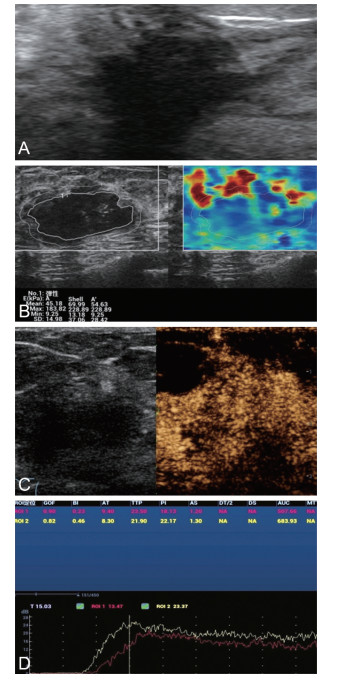

Clinical value of ultrasonography combined with shear wave elastography for the assessment of molecular subtypes of breast cancer

BI Weipei, SHI Yan, WANG Lingling, ZHANG Hui, CUI Zhen

2023, 21(12): 2009-2013. doi: 10.16766/j.cnki.issn.1674-4152.003278

Abstract:

Objective  To investigate the relationship between qualitative and quantitative parameters of contrast ultrasound combined with shear wave elastography and different molecular staging of breast cancer.  Methods  Fifty-two patients with suspected malignant lesions detected by mammography and/or routine ultrasonography and confirmed as invasive breast cancer by the Department of Pathology of the First Affiliated Hospital of Bengbu Medical College from October 2022 to July 2023 were enrolled, and immunohistochemical results were collected, and were divided into three groups of breast cancer types based on the pathological results: luminal type (26 cases), HER-2 type (17 cases) and triple-negative (9 cases). Ultrasonographic and elastographic features of these patients were observed and time-intensity curves of breast cancer lesions were analyzed using ultrasonographic software, and ultrasonographic features of mass and quantitative parametric indicators of elastography were analyzed in relation to different molecular subtypes of breast cancer.  Results  There were significant differences in histological grading and lymph node metastasis between different breast cancer subtypes (P < 0.05), HER-2 positive breast cancer lesions were more likely to have a rapidly enhancing enhancement pattern(n=15, 88.2%, P < 0.05) as well as hyper-enhancing enhancement features(n=14, 82.4%, P < 0.05), and ultrasound elastography Emax values and the quantitative contrast parameter PI were significantly higher in patients with HER-2 subtype breast cancer than in luminal and triple-negative types [(170.32±53.35) kPa vs. (119.26±36.95) kPa vs. (155.80±73.59) kPa, P=0.006); (25.22±5.79) dB vs. (20.82±4.80) dB vs.(24.51±6.75) dB, P=0.030].  Conclusion  There is a correlation between ultrasound enhancement features and perfusion parameters combined with quantitative parameters of shear wave elastography and different molecular subtypes of breast cancer, so ultrasound analysis and quantitative parameters can be used as a more objective and accurate means of detection, which can provide a reference basis for clinical diagnosis of breast cancer, individualized treatment and prognostic analysis.